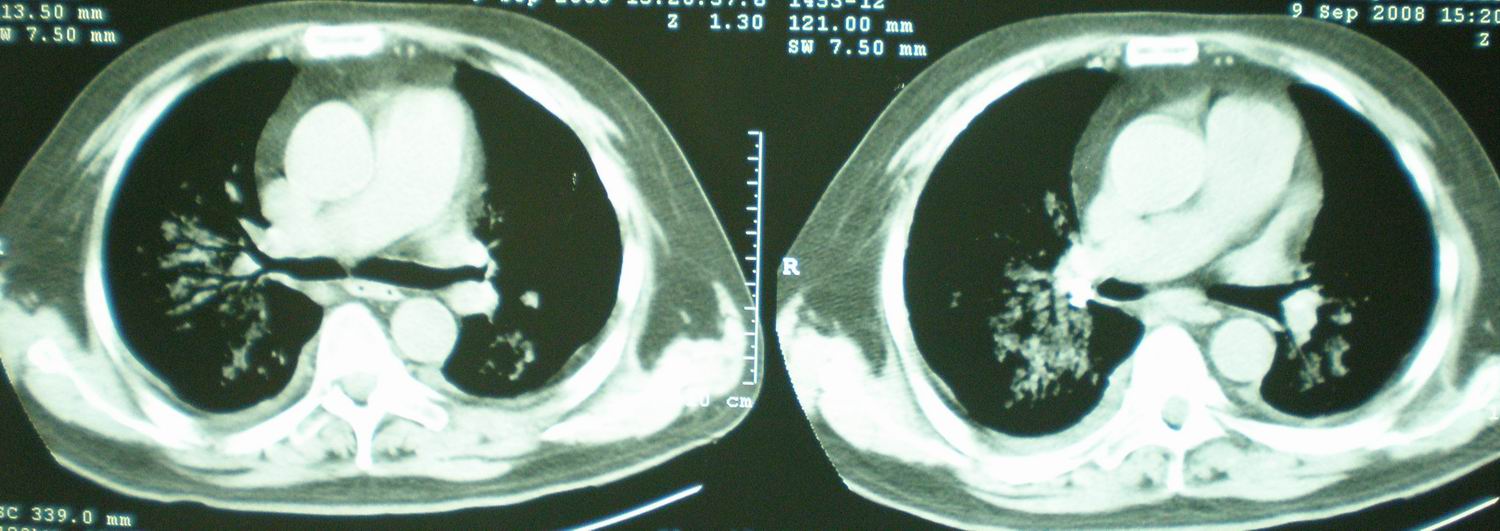

2008年9月8日ct片:

我仔细看了下病人的出院小结,当时情况危急,诊断里有1型呼衰。心包周围的是脂肪密度。结合三次ct扫描的图象分析,个人认为:1、病人目前肺部病灶基本消失,双侧胸腔内少量积液,抗结核治疗才一个多月,就算是结核,抗结核治疗有效果,为何效果如此好,一点纤维灶的痕迹都没有呢,再就是患者做过气管镜检查及活检、痰检均未找到结核的证据。所以不支持结核的诊断。

2、结合现在的ct片,考虑:肺水肿及真菌感染,双侧胸腔积液。

急性呼吸窘迫综合征,肺水肿,与激素减量太快有关.双侧胸腔积液.

机遇性感染。双肺实质满布。且以肺门周围为主。不象结核。